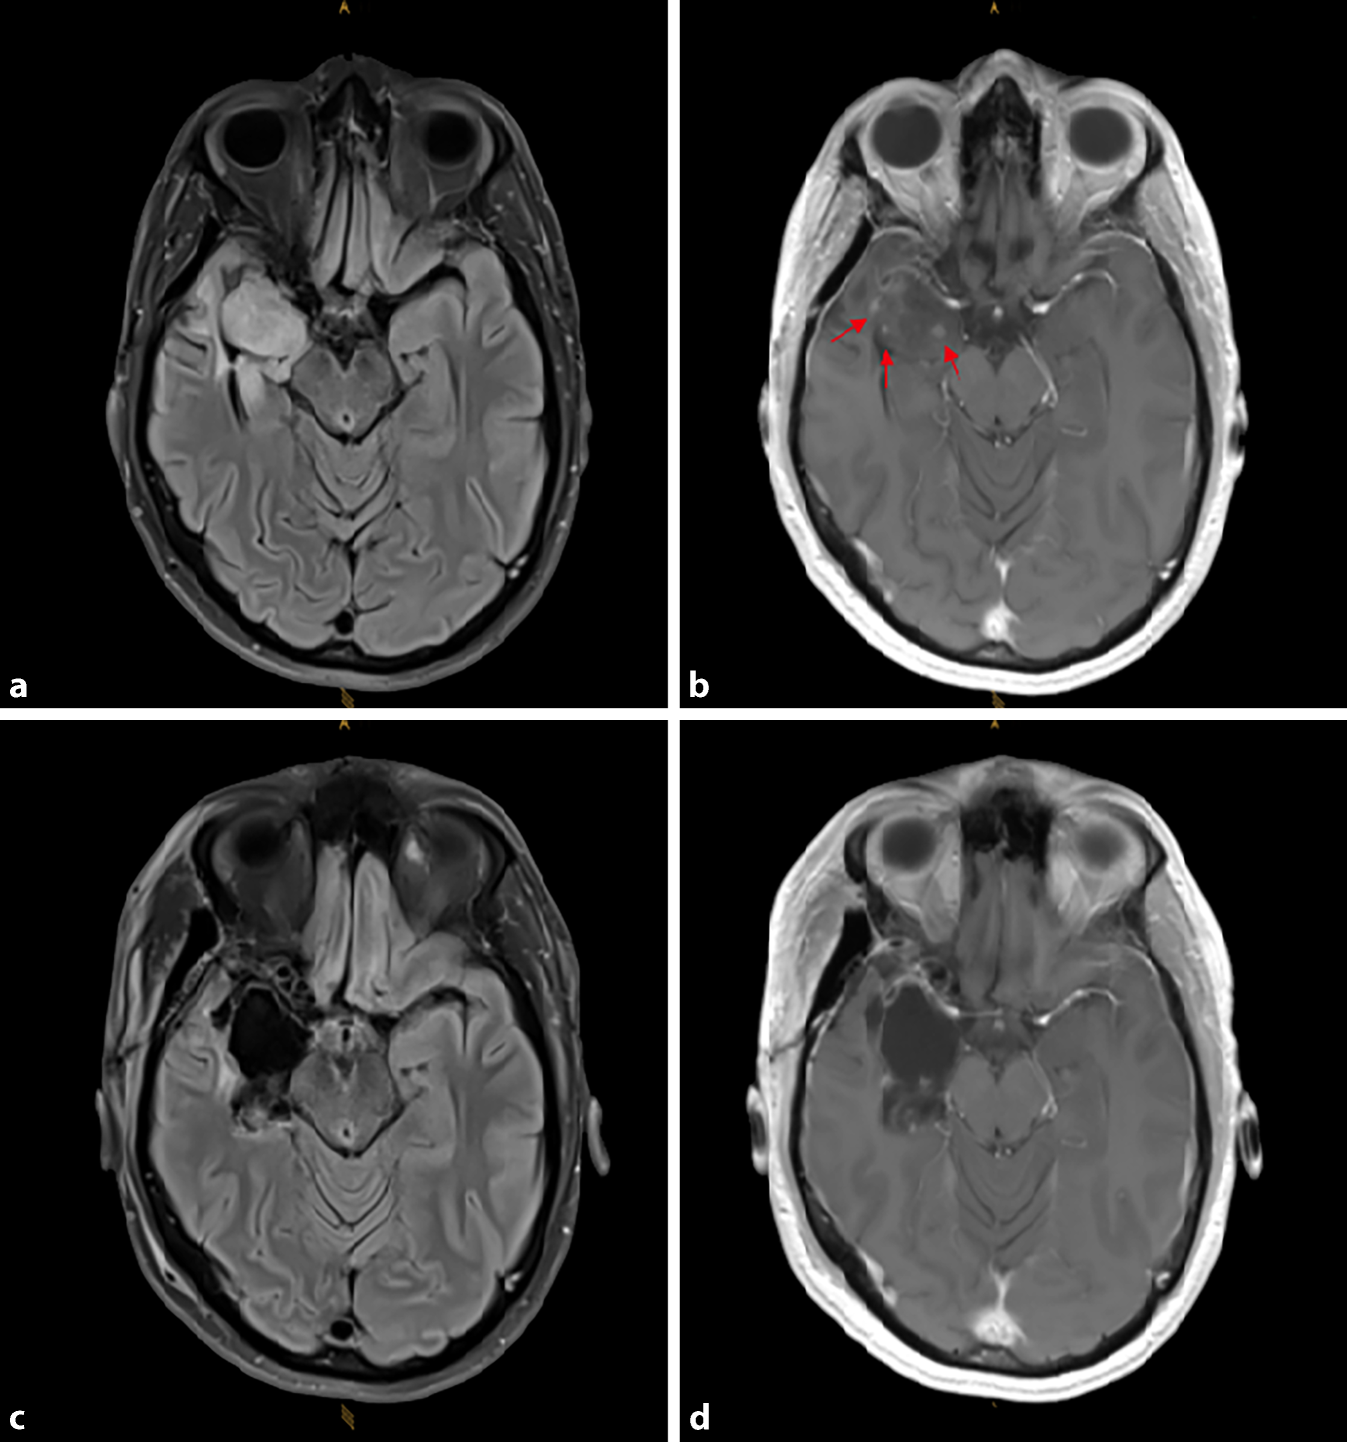

Im November 2021 berichtete der Patient über eine neuerliche Anfallszunahme mit nahezu täglichem Auftreten seit etwa 3 Monaten. Bildgebend zeigte sich ein stabiler Befund ohne Zeichen eines Tumorwachstums. Eine Add-on-Therapie mit Lacosamid wurde gestartet. Zusätzlich wurde, auch wenn sich bildgebend kein Progress zeigte, bei vorliegender klinischer Verschlechterung eine Chemotherapie mit Temozolomid eingeleitet. Ziel der Tumortherapie war, die Anfallsproblematik positiv zu beeinflussen. Initial zeigte sich unter Chemotherapie ein Rückgang der Anfallsfrequenz, nach 4 Zyklen aber dann wieder eine Verschlechterung. Auch bildgebend konnte dann zu diesem Zeitpunkt unter Therapie ein progredientes Tumorwachstum, vor allem rechts temporomesial im Bereich der Amygdala beziehungsweise um dieses Areal und auch entlang des Hippocampus festgestellt werden. Als möglicher bildgebender Hinweis einer Malignisierung des Tumors fanden sich neue punktförmige Kontrastmittelanreicherungen im Bereich der Amygdala (Abb. 1a, b). Daraufhin wurde bei klinischem und bildgebendem Progress eine Re-OP empfohlen. Präoperativ kam es zu einer laufenden Verschlechterung der Anfallssituation mit bis zu 20 Anfällen pro Tag. Medikamentös wurde zusätzlich eine Therapie mit Clobazam etabliert. Die OP wurde priorisiert und es erfolgte eine Rezidiv-Tumorexstirpation mit Entfernung der Tumoranteile rechts temporomesial (Abb. 1c, d). Resttumoranteile im Bereich der Sehbahn rechts wurden bewusst aus funktionellen Gründen belassen.

a,b Progrediente FLAIR-Signalveränderungen rechts temporomesial (a T2-FLAIR), neu aufgetretene punktförmige kontrastmittelaufnehmende Läsionen (rote Pfeile) im Bereich der Amygdala rechts (b T1-KM). c,d Postoperative cMRT nach Entfernung der Tumoranteile rechts temporomesial (c T2-FLAIR, d T1-KM). (© Leibetseder)